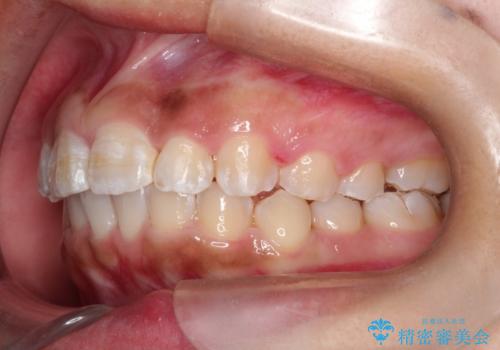

マウスピース矯正で前歯のガタツキを改善! ワイヤー矯正併用でかみ合わせもしっかり治します

- 前歯のガタツキが気になると来院されました。

マウスピース矯正治療を選択しました。

この症例では、奥歯のかみ合わせの改善を目的にワイヤー矯正を併用しました。奥歯のかみ合わせをより緊密にするため、また短期間に治療するためにはワイヤー矯正が適していることがあります。